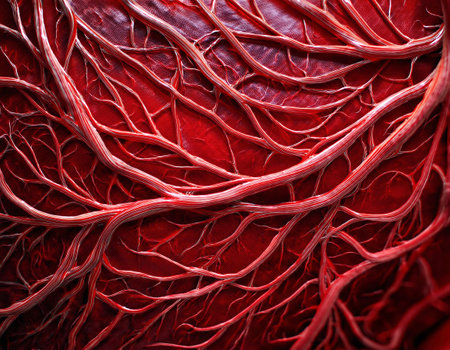

Detailed visuals showcase the complex network of blood vessels in human anatomy.

A detailed view of red blood vessels intertwines across a soft gradient background. The intricate network showcases the complexity of human circulation highlighting the various sizes and shapes of the vessels

A close up of a red, twisted, and tangled mass of red tissue. Concept of chaos and disorder, as the tangled mass of tissue seems to be in a state of disarray